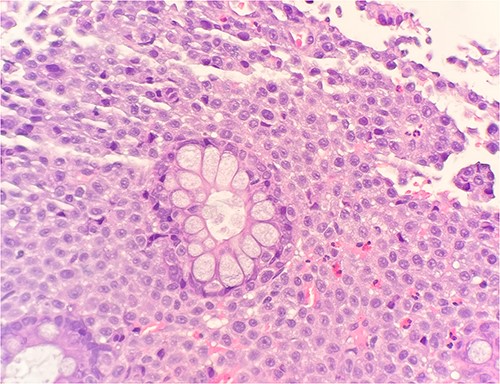

Microscopic examination shows extensive involvement of the bladder wall by sheets of small round blue tumor cells showing cleaved and irregular nuclear contours and conspicuous nucleoli. Mitotic activity is frequent and majority of cells show scant amphophilic cytoplasm with few foci showing more abundant bubbly cytoplasm and others with clear foamy cytoplasm (Fig. 1). A rare foci of finely granular brown pigment representing melanin and moderate cytological atypia in a small area of surface urothelium. Similar morphological features are seen in colonic biopsy specimens (Fig. 2).

Microscopic examination reveals sheets of round cell between unremarkable colonic crypts. H&E stain 40×.